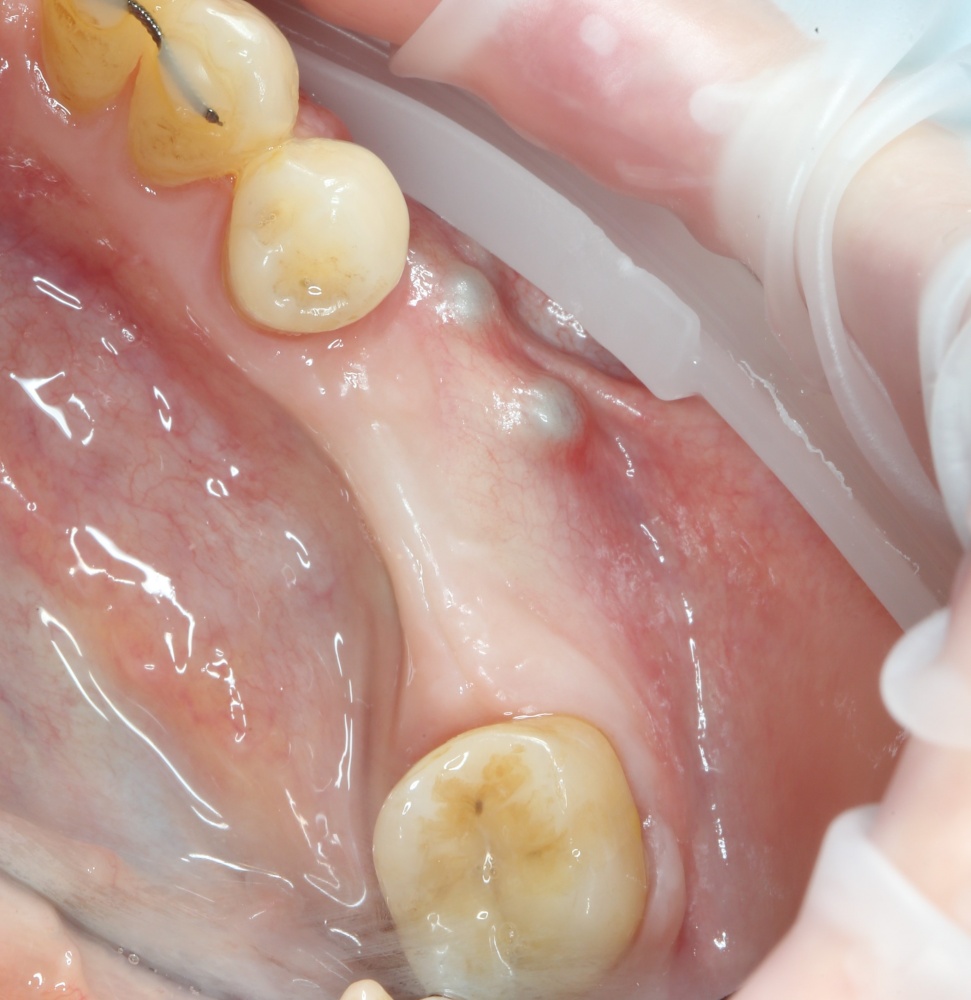

Через 4 месяца мы можем оценить результат проведенной операции:

A09A6611 (2) A09A6612 (2)

На фотографиях видно, насколько атрофировался костный блок. Именно поэтому при планировании мы увеличили объемы блока на величину этой атрофии.

Теперь делаем разрез и открываем импланты:

A09A6620 (2) A09A6621 (2)

На фотографиях хорошо видно, какие изменения произошли с областью операции за четыре месяца. Пересаженный костный блок интегрировался настолько хорошо, что частично заросли заглушки имплантов. Такое нередко происходит, именно поэтому в подобных случаях я предпочитаю импланты с конической ортопедической платформой — их легче открывать.

Нам остается просто поставить формирователи десны:

A09A6628 (2) A09A6629 (2)

и подождать, пока вокруг них сформируется плотная слизистая оболочка. Потом мы направляем пациента к ортопеду для протезирования.